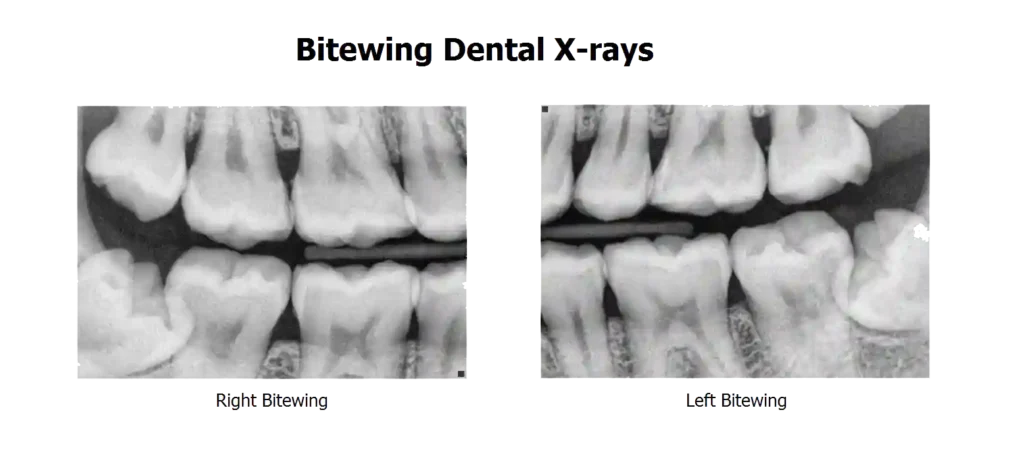

نقش رادیوگرافی در تشخیص

رادیوگرافی کمک میکند:

- بررسی موقعیت دندان

- بررسی آسیب به دندان دائمی

- تشخیص عفونت